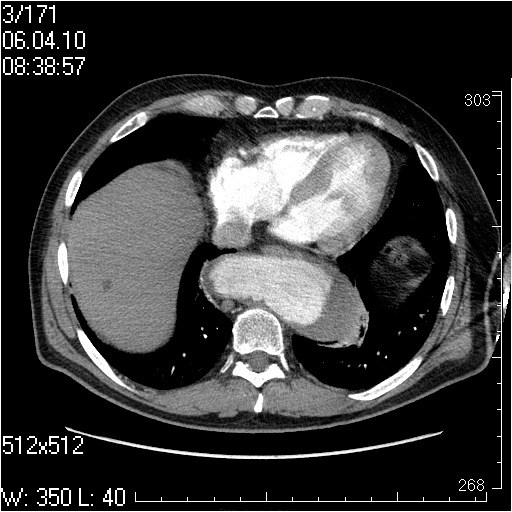

Грудной отдел аорты

Пожилой мужчина, жалоб в настоящее время не предъявляет.